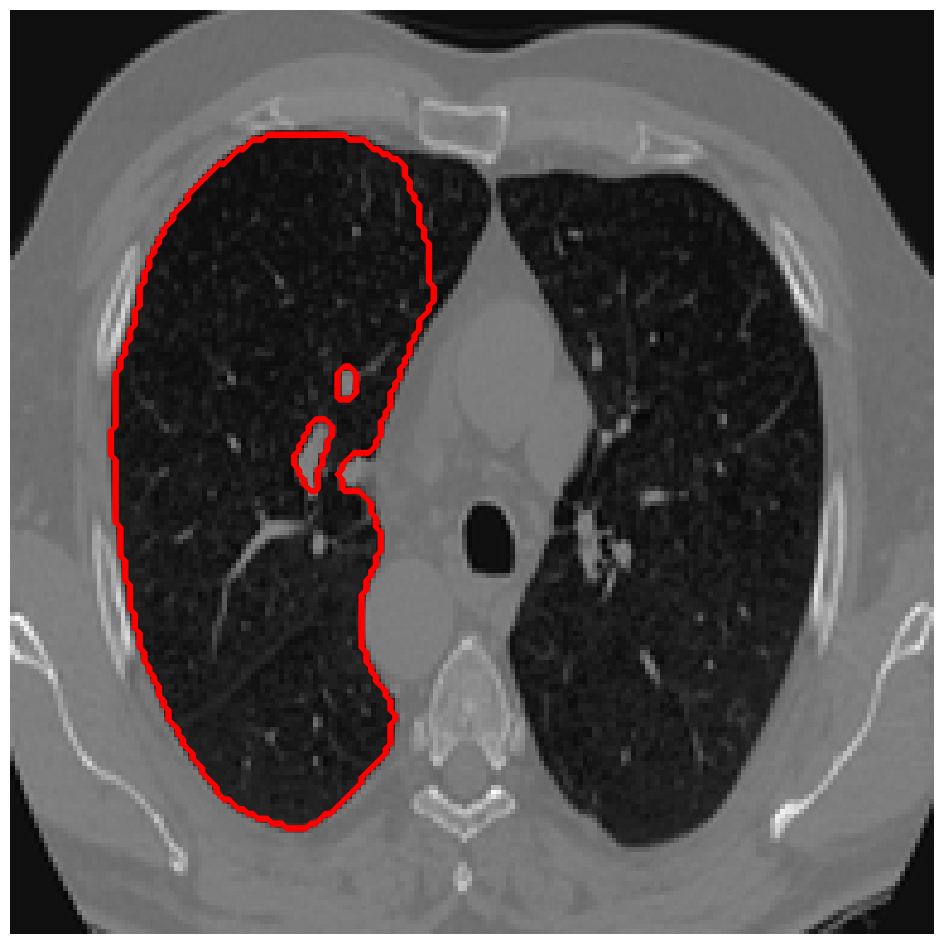

Figure 3: A sample result on the Lung data. We display the input image with the user input \mathcal{M}, the ground truth (GT) and results from the four methods. Moreover, we show comparisons with the model (4) solved in a variational framework with both Total Variation (TV) and Euler Elastica as explicit regularisation, as well as a comparison with the model solved in a Deep Image Prior framework.

Figure 4: A sample result on the Lung data. We display the input image with the user input \mathcal{M}, the ground truth (GT) and results from the four methods. Moreover, we show comparisons with the model (4) solved in a variational framework with both Total Variation (TV) and Euler Elastica as explicit regularisation, as well as a comparison with the model solved in a Deep Image Prior framework.

In Figures 3 and 4 we show two select images from the test set for the Lung images to qualitatively show some results. To begin, we show some results of the model (1) solved with a Total Variation (TV) [21] regulariser, and with a Euler Elastica [22] regulariser. In addition, we show a result with the model (1) in a typical Deep Image Prior framework (i.e. training a network specifically for that image without the explicit regularisation in the loss function, employing early stopping). We see that the result from M4 is an improvement over the TV and Elastica models, whereas results from the DIP example is comparable. However, the DIP example requires a new network trained specifically for the new image, whereas our result is acquired after training. In addition to the explicit regularisation comparison, we also display the results from the four methods (all of which are trained previously on 222 images and used for prediction). Moreover some quantitative results are shown in table 1, which shows the mean DICE score and standard deviation on the 16 images in the test set.